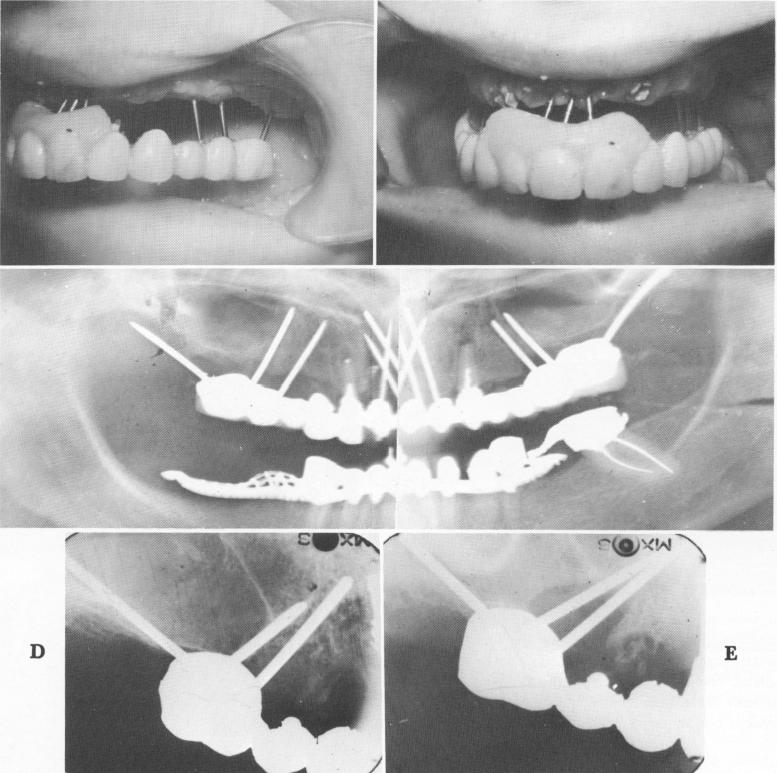

Fig. 14-20. A and B, Often a bridge can be removed with all of the triplant pins still attached to it and still diverging from each other. Very seldom will any fibrous tissue be attached to the pins, such as is usually the case with the post type and blade implants, indicating the lack of a physiologic pseudomembrane attachment. C, A Panorex showing the entire prosthesis and the diverging pins just prior to its removal. D, Periapical radiograph taken immediately after pins were inserted. E, Six months' postoperative radiograph reveals large breakdown of bone around the two mesially directed pins, which were placed too close together and too close to the buccal plate of bone.